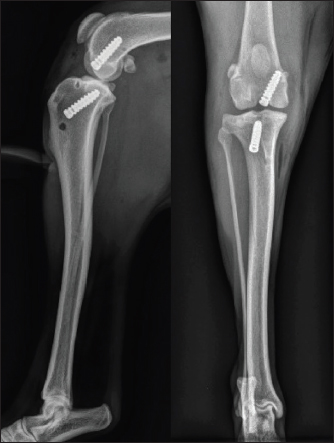

On day 1 post-surgery, the dog was walking on her operated leg with moderate lameness. During each postoperative consultation, two x-rays were performed (face and profile), as well as an orthopedic examination. A LOAD questionnaire was also completed. After 2 weeks, moderate lameness was observed, and radiographs showed thickening of the patellar tendon and moderate synovial inflammation; the LOAD score was 21/52. After 1 month, moderate lameness was persistent, radiographs still showed thickening of the patellar tendon and moderate synovial inflammation; the LOAD score was 13/52. After 2 months, moderate lameness was still observed, radiographs had not evolved, and the LOAD score was 7/52. After 3 months, mild lameness was observed, a mild posterior drawer was reported at orthopedic examination and moderate synovial inflammation was observed on radiographs (Fig. 6); the LOAD score was 7/52. After 6 months, very mild lameness was observed, a mild posterior drawer was reported at orthopedic examination and a resolution of the synovial inflammation was seen on radiographs (Fig. 7); the LOAD score was 5/52. After a year, a persistent yet stable mild posterior drawer was reported at the orthopedic examination but was not associated with any lameness, and the LOAD score was down to 2/52.

Fig. 6. 3-month postoperative radiographic views of dog's right pelvic limb from side (left) and front (right).